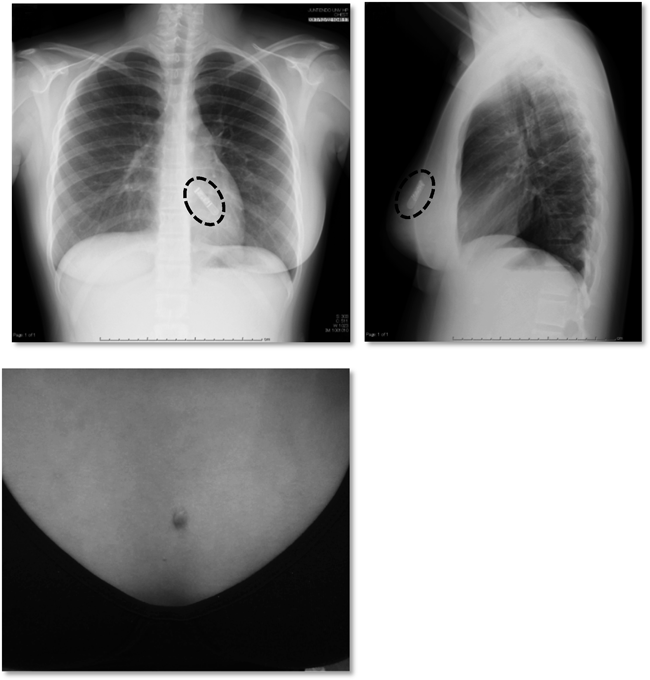

造影心臓CT(Fig. 2)

Michaelらの国際分類でinterarterial1)(壁内走行を伴わず大動脈と肺動脈の間を走行する)の右冠動脈の起始部異常を認めた.

Fig. 2 Cardiac CT imaging

Cardiac CT confirmed that the right coronary artery originated from the anterior 1 o'clock direction of the aortic valve and ran between it and the pulmonary artery. The arrow indicates the right coronary artery.

Fig. 3 Chest X-ray and wound condition after ICM implantation

A chest X-ray after ICM implantation is shown (upper figure). The dashed round frame indicates the ICM device implanted subcutaneously. The skin condition (lower figure) about 1 month after ICM implantation was good, and the proceedings have passed without any complaints such as discomfort.